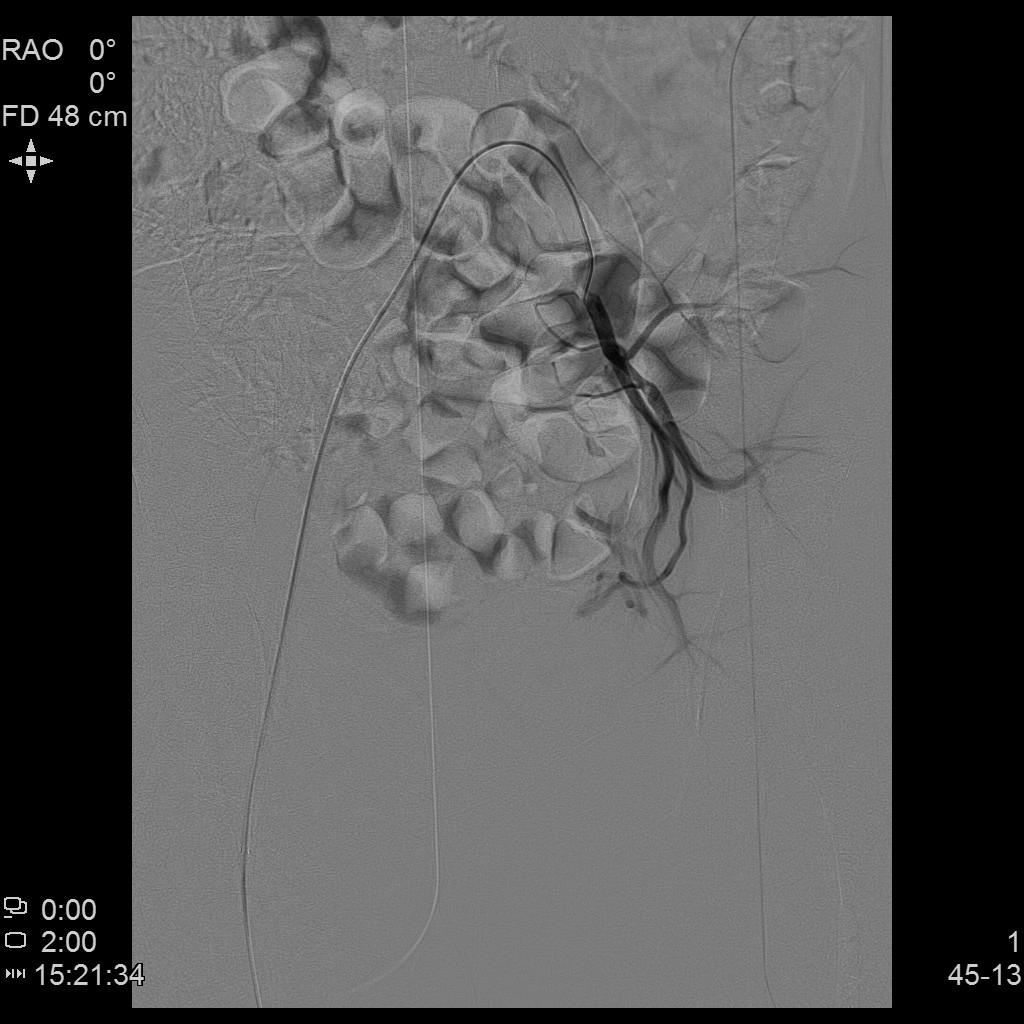

腹主动脉造影

左侧子宫造影

右侧子宫动脉造影